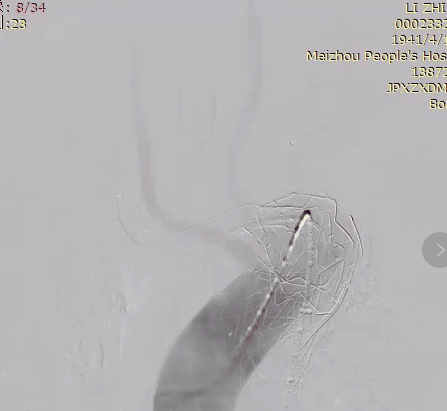

重建LSA

从右侧股动脉导入导丝,并超选进LSA的内嵌分支开口后,置入Viabahn覆膜支架并释放,为降低LSA分支支架远期狭窄的风险,再次在LSA远端再释放一个裸支架。

超选导丝进入LSA